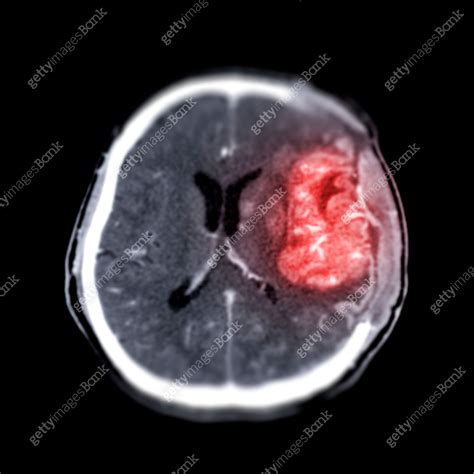

A brain cancer CT scan, or Computed Tomography scan, is a sophisticated diagnostic imaging test that uses X-ray technology to capture detailed cross-sectional images of the brain. Unlike a standard X-ray, which produces a single flat image, a CT scan takes multiple images from various angles and uses computer processing to create comprehensive "slices" of the internal structures of the head. This allows radiologists to examine the brain tissue, blood vessels, and bone structures in high definition.

Doctors often order this scan if they suspect an abnormality such as a tumor, cyst, or inflammation. By visualizing the physical landscape of the brain, medical experts can identify the location, size, and shape of potential growths, which is crucial for determining the next steps in a clinical treatment plan.